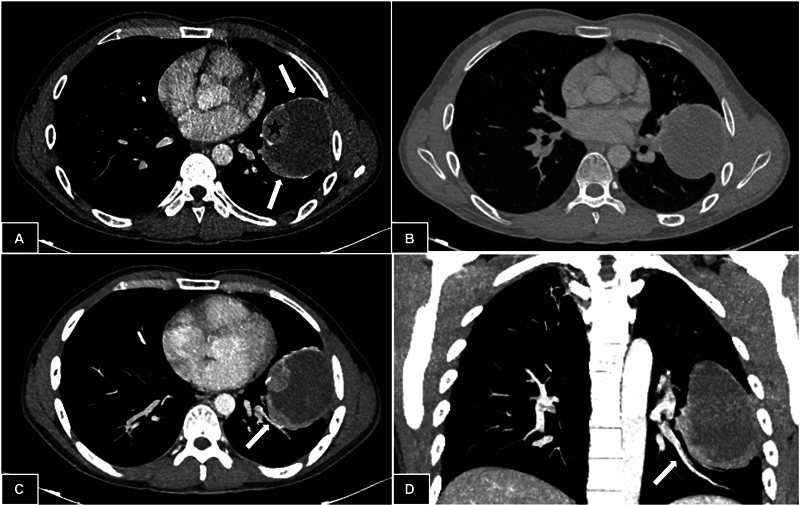

Pulmonary sclerosing pneumocytoma is a rare benign neoplasm typically seen in middle-aged women. The exact preoperative diagnosis is quite challenging considering its nonspecific clinical and radiologic features along with complex histology. Moreover, obtaining an exact histopathological diagnosis can be difficult especially with the small biopsy specimens. Most patients are generally asymptomatic with incidental detection of peripheral, homogenous, solitary pulmonary nodule. It is essential to differentiate it from other mimickers including malignant lesions as limited surgical resection is curative in these cases without adjuvant therapy. We present a rare giant cystic variant of pneumocytoma, in a young male, which was initially mimicking inflammatory myofibroblastic tumor even on preoperative histology.

Abstract Image